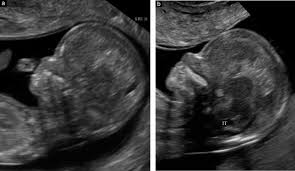

The 11 14 Week Scan Chapter 1 from sonoworld.com It should not be confused with the nuchal fold, which is seen in the second trimester. But many babies with down's syndrome have an increased amount. That's why the nt scan is used to help screen for down's syndrome. I'm still waiting for my follow up appointment after my scan results which my gp has said look normal. As i'm 3 months late for this appointment i rang the hospital and spent over an hour getting absolutely nowhere. The first trimester screen won't harm you or your baby. The nt scan measures the thickness of the fluid at the back of your baby's neck. It is a special ultrasound scan which is performed to specifically measure a tiny bit of fluid that lies under the baby's skin behind the neck known as the nuchal translucency (nt).

The 11 14 Week Scan Chapter 2 from sonoworld.com Some babies with increased fluid don't have down syndrome or any other abnormality. This is when they measure the fluid at the back of the baby's neck. The nuchal translucency normal range chart is a guideline during this scan. But if it is between 3 and 3.5mm, then it is considered high (6) (7). An nt scan is a common screening test that occurs during the first trimester of pregnancy. To be more precise, the normal nt ranges from 1.2 to 2.1mm when the crl is 45mm. Also, a negative or normal result (one that shows a decreased risk) does not mean that the baby will not have a chromosome abnormality. There are a lot of things that can cause a large nt, including a chromosomal abnormality or heart defect or nothing at all.